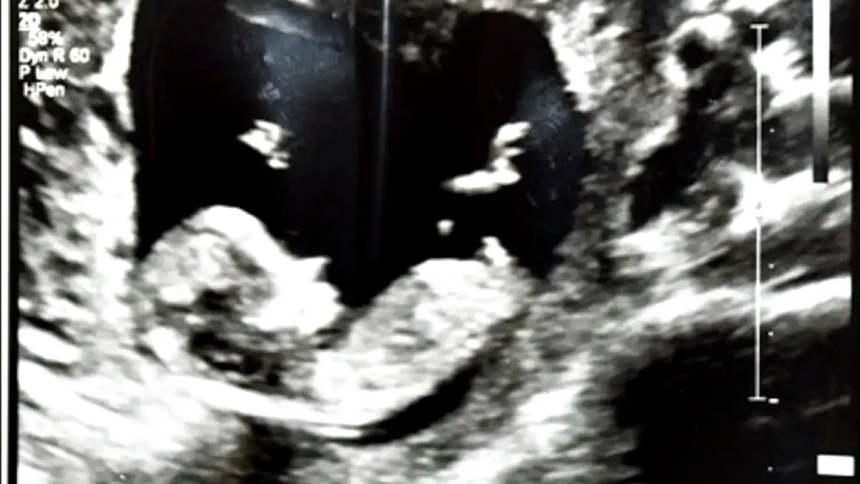

Junto a su cuerpo, las autoridades encontraron un casquillo de bala y una imagen de ultrasonido. Este hallazgo evidenció el embarazo que había sido motivo de conflicto entre la pareja.

Lo que se indicó, es que la víctima y madre de un niño pequeño, se encontraba en el primer trimestre de gestación cuando terminó asesinada.